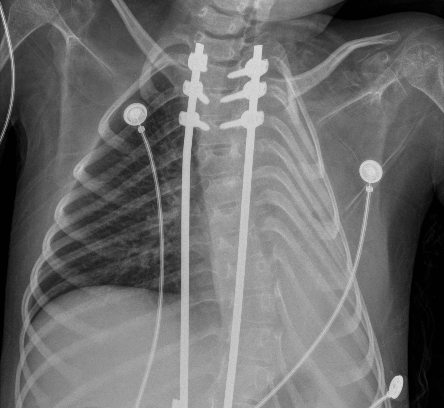

El primer día de internación, se solicitó una radiografía, que evidenció una atelectasia masiva del pulmón izquierdo (Figura 1). En este contexto, se optimizó la THB e interfaz de VNI. Para optimizar la presurización del sistema respiratorio, se cambió la interfaz nasal por una oronasal. El paciente permaneció con su equipo de VNI durante las 24 horas y solo se desconectó para realizar THB. Se monitorearon los signos vitales con el objetivo de mantener una saturación ≥94 % con la menor FiO2 posible. Como parte del plan de THB, se programó ventilación percusiva intrapulmonar (VPI) y CA dos veces al día durante cinco días consecutivos. Se utilizó un equipo de VPI The Impulsator® de Percussionaire con circuitos Phasitron®. Se emplearon 10 minutos en modo easy para favorecer la movilización de secreciones más distales y 10 minutos en modo hard para garantizar el reclutamiento alveolar. Se utilizó una relación I/E de 1:1 o 3:1, según tolerancia, con un rango de presión de la vía aérea entre 10-30 cmH2O y una presión de trabajo de 2-4 bares. Se continuó con CA, con una presión de insuflación de +30 cmH2O y una presión de exuflación de -40 cmH2O, junto con asistencia manual de la tos, con el objetivo de movilizar secreciones de vías aéreas proximales. En el segundo día, ante la ausencia de mejoría, se optimizó el equipo de soporte ventilatorio cambiando la VNI domiciliaria por un equipo de soporte vital. Se colocó un Trilogy 202 (Respironics®) en modalidad binivel, con monorama a fuga, en modo asistido controlado por presión, con humidificación activa y una interfaz facial total. En el tercer día, no se implementaron cambios en la programación de la VNI, y se continuó con la misma THB. En el cuarto día, se interconsultó al servicio de endoscopía respiratoria, quienes otorgaron un turno a la brevedad para realizar una fibrobroncoscopía con intubación e instilación de alfa dornasa, junto con VPI en línea con ventilación mecánica, como método invasivo de resolución de atelectasias. En el quinto día, se realizó una nueva radiografía, que mostró una reducción significativa del área atelectásica (Figura 2), lo cual se objetivó con mejoría clínica. Esto permitió descender las presiones, y se volvió a su programación habitual. Asimismo, se finalizó el uso de la VPI y se continuó únicamente con CA y asistencia manual de la tos. Después de 24 horas, el paciente estaba llevando a cabo dos períodos de 3 horas de desconexión de la VNI a aire ambiente. A las 48 horas, se logró la desvinculación de la VNI diurna, con reconexión nocturna a su equipo domiciliario e interfaz nasal. En el séptimo día, se confirmó la resolución de la atelectasia en la radiografía (Figura 3), quedando suspendida la intervención de endoscopía respiratoria. En el octavo día, se le otorgó egreso hospitalario. En la Figura 4, se resume la evolución del paciente.